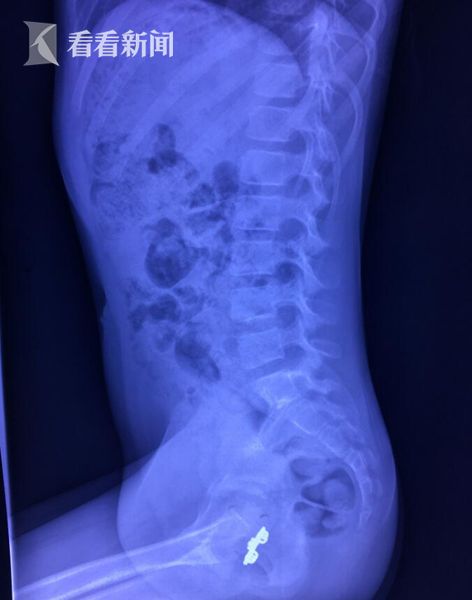

直到遇到一位泌尿科李主任,「正常孩子不可能會出現這樣的情況,更何況這個情況從三年前才開始」,於是安排楠楠進行X光檢查,果真在她的陰道內找到一個「金屬髮夾」。醫師先用透過膀胱鏡檢視,發現該髮夾在距離陰道口約6公分處,已被肉芽層層包住,經過好一番功夫,才順利將長2.5公分,寬1.4公分的生鏽髮夾取出。